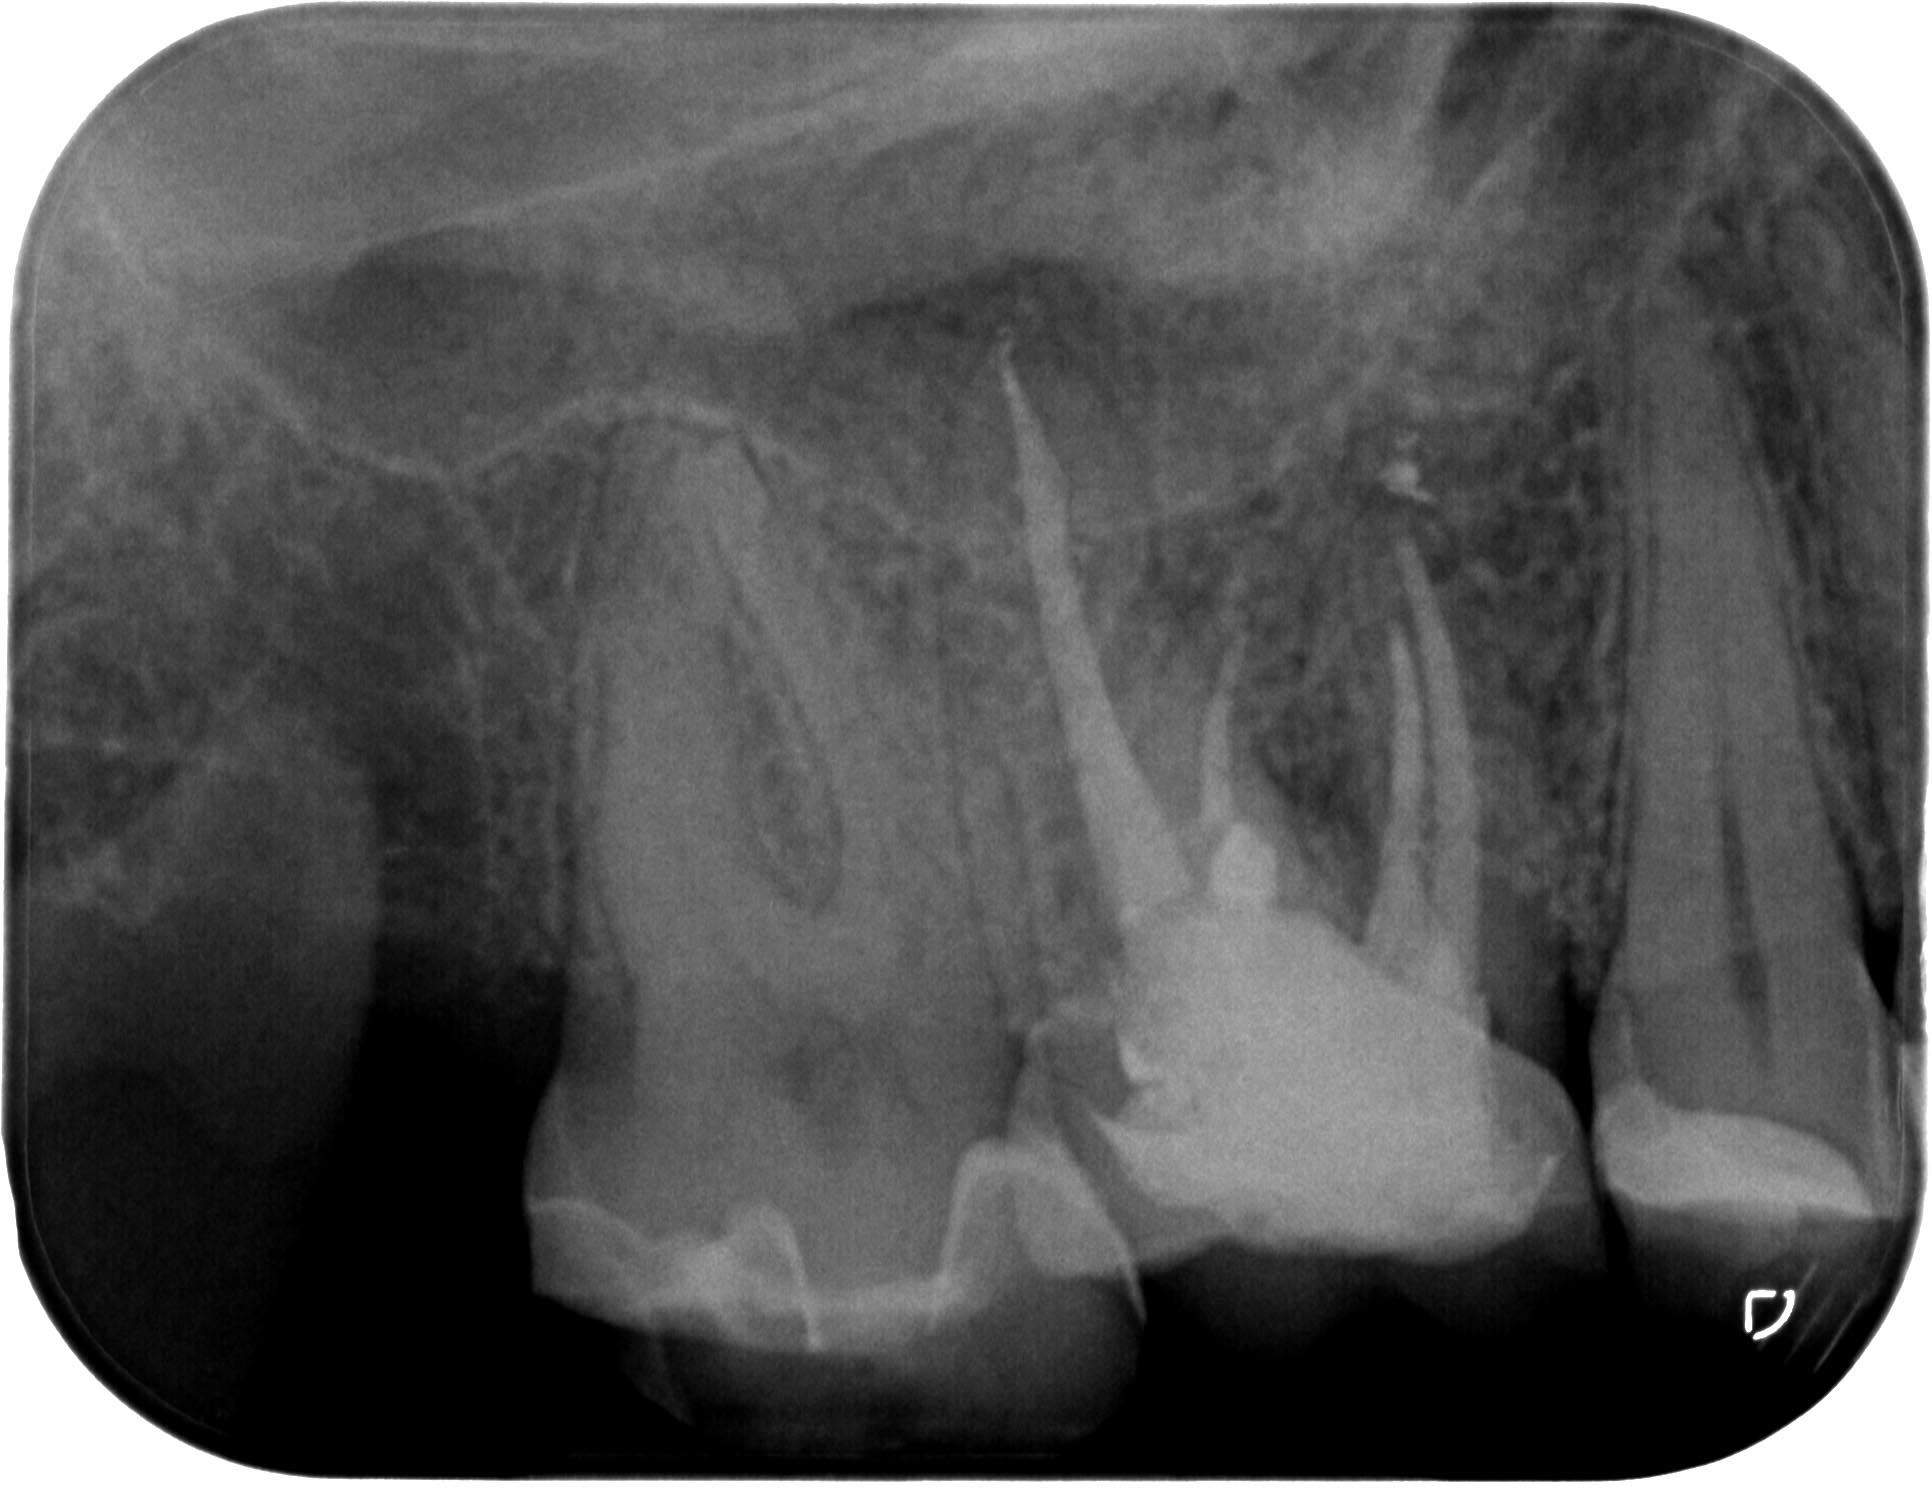

sg_16-3-2

1932 × 1490

Unauffälliges Röntgenbild (Teil 2)